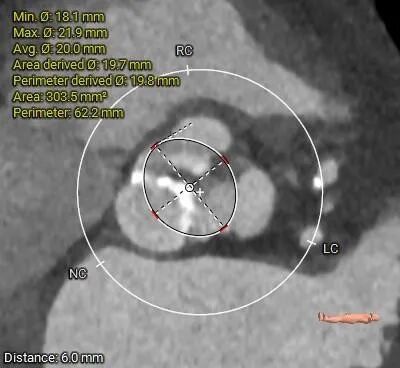

术前CT评估

• 三叶式主动脉瓣,瓣叶增厚,R-L交界增厚粘连,轻度钙化,钙化主要沿无冠窦瓣缘分布;LVOT近似直筒型;

• 瓦氏窦内径尚可,STJ小于30mm,升主动脉无扩张,瓣上40mm处测得约33.7mm;

主动脉根部评估

• 三叶式主动脉瓣,瓣叶增厚,R-L交界疑似增厚粘连,轻度钙化,钙化主要沿无冠窦瓣缘分布,LVOT近似直筒型,预估假体瓣膜植入锚定难度适中,结合瓣环及瓣上分析尺寸,选择TaurusElite AV23瓣膜,可以保证充分锚定力且径向支撑性好;